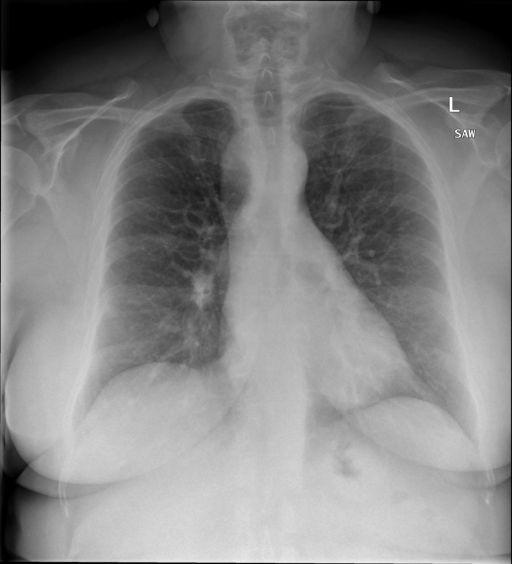

- (1)准备[诊疗报告(中文)](./data/Xray/openi-zh.json)和[X光影像](https://pan.baidu.com/s/13GBsDMKf6xBZBSHpoWH_EA?pwd=k9sh)在`data/Xray`文件夹下; - (2)开始训练: ```bash # 设置CUDA变量,主要是为了解决有时候直接训练而出现无法正确加载到显卡问题 export CUDA_VISIBLE_DEVICES=0,1,2,3 # 开始训练 bash finetune_XrayGLM.sh ``` 这里的复现过程非常简单,主要是很多过程我们都为大家准备好了,大家可以随时复现一个自己的`XrayGLM`。 ### 4.模型训练(通用) ## 效果展示 *以下效果来自于**低质量**的数据训练和权重 影像诊断: |X光影像|诊疗报告(医生)|XrayGLM| |:-|:-|:-| |![](./data/Xray/2_1.png)|根据X射线图像,心脏大小正常,肺部看起来很清晰。已经排除了肺炎、积液、水肿、气胸、腺病、结节或肿块的存在。该发现表明一切正常。换句话说,总体印象是胸部正常。|X光片显示,心脏大小正常。肺部没有气胸或胸腔积液的证据。骨骼结构看起来没有任何异常。总的来说,X光片表明没有发现急性心肺疾病的迹象。| |![](./data/Xray/2882_1.png)|X光图片显示没有扭曲的区域、可疑的骨质不透明度或胸腺积液。心脏大小轻微增大,但非常稳定。此外,没有气胸的证据,肺野也正常。总体来说,X光片显示没有急性心脏异常,但要注意轻微的心脏扩大。|X光片显示,心脏大小正常。肺部和纵隔轮廓清晰,没有气胸或胸腔积液的证据。骨骼结构完整,没有任何急性异常。| |![](./data/Xray/2577_1.png)|心影形态在正常范围内。没有急性骨质异常。有可能出现没有明显的吸水或肺实质状况的线索。没有大面积积液或气胸。有可能怀疑其有误吸或肺实质问题。为了确诊和治疗,可能需要进行适当的影像学随访。|心脏大小正常,肺部和纵隔轮廓清晰。没有急性异常或活动受限的证据。没有任何明显的气胸、胸腔积液或肺不张的迹象。此外,也没有发现任何局灶性骨质异常或其他急性疾病。| 多轮对话: |X光影像|诊疗报告(医生)| |:-|:-| |![](./data/Xray/861_1.png)|右侧主动脉突出观察到。心脏大小正常。胸部未发现明显的肺气肿、胸膜积液或可疑的肺部病变。报告指出已知右侧主动脉情况正常。| ```bash >> X光影像路径:./data/Xray/861_1.png >> 用户:这是一张什么图? >> XrayGLM:这张图片显示的是一张肺部检查的X光片。 >> 用户:请描述这张胸部X光片的诊断结果 >> XrayGLM:心脏大小正常,肺部清晰。没有急性心肺疾病的证据。 >> 用户:是否存在肺气肿? >> XrayGLM:没有肺气肿。心脏大小正常,肺部清晰。没有发现急性心肺疾病的证据。 >> 用户:平时饮食该注意什么? >> XrayGLM:饮食应该健康,均衡。建议增加蛋白质的摄入量,因为蛋白质有助于维持肌肉和骨骼的健康。多食用蔬菜、水果、全谷物以及健康的脂肪来源如橄榄油、鱼类等可以帮助获得足够的维生素和矿物质。此外,避免过度饮酒或吸烟,这些习惯可能会对心脏健康产生负面影响。 ``` ## 未来展望 1. 模型的能力更多来源于数据的支持,`OpenI-zh`作为微调数据集,其数据量足以支持研究,在更广泛的任务和性能表现上,我们认为**在大规模数据集上预训练并在高质量少量数据集上微调是一种可行的方案**; 2. 普遍意义的理解上,视觉多模态模型=视觉模型+语言模型。除了需要关注视觉模型信息与语言模型输出的搭配外,还需要**额外关注到语言模型的加强,在人机的对话中,尤其是医疗语言模型的问答上,除了专业的医疗问题回答,带有人文情怀的有温度的回答更应该是我们追寻的目标**。 ## 项目致谢 1. [VisualGLM-6B](https://github.com/THUDM/VisualGLM-6B)为我们提供了基础的代码参考和实现; 2. [MiniGPT-4](https://github.com/Vision-CAIR/MiniGPT-4)为我们这个项目提供了研发思路; 3. ChatGPT生成了高质量的中文版X光检查报告以支持XrayGLM训练; 4. [gpt_academic](https://github.com/binary-husky/gpt_academic)为文档翻译提供了多线程加速; 5. [MedCLIP](https://github.com/RyanWangZf/MedCLIP) 、[BLIP2](https://huggingface.co/docs/transformers/main/model_doc/blip-2) 、[XrayGPT](https://github.com/mbzuai-oryx/XrayGPT) 等工作也有重大的参考意义; ![](./assets/images/mpu.png) 这项工作由[澳门理工大学应用科学学院](https://www.mpu.edu.mo/esca/zh/index.php)硕士生[王荣胜](https://github.com/WangRongsheng) 、[段耀菲](https://github.com/IsBaSO4) 、[李俊蓉](https://github.com/lijunrong0815)完成,指导老师为檀韬副教授、[彭祥佑](http://www.patrickpang.net/)老师。 *特别鸣谢:[USTC-PhD Yongle Luo](https://github.com/kaixindelele) 提供了有3000美金的OpenAI账号,帮助我们完成大量的X光报告翻译工作 ## 免责声明 本项目相关资源仅供学术研究之用,严禁用于商业用途。使用涉及第三方代码的部分时,请严格遵循相应的开源协议。模型生成的内容受模型计算、随机性和量化精度损失等因素影响,本项目无法对其准确性作出保证。即使本项目模型输出符合医学事实,也不能被用作实际医学诊断的依据。对于模型输出的任何内容,本项目不承担任何法律责任,亦不对因使用相关资源和输出结果而可能产生的任何损失承担责任。 ## 项目引用 如果你使用了本项目的模型,数据或者代码,请声明引用: ```bash @misc{wang2023XrayGLM, title={XrayGLM: The first Chinese Medical Multimodal Model that Chest Radiographs Summarization}, author={Rongsheng Wang, Yaofei Duan, Junrong Li, Patrick Pang and Tao Tan}, year={2023}, publisher = {GitHub}, journal = {GitHub repository}, howpublished = {\url{https://github.com/WangRongsheng/XrayGLM}}, } ``` ## 使用许可 此存储库遵循[CC BY-NC-SA](https://creativecommons.org/licenses/by-nc-sa/4.0/) ,请参阅许可条款。